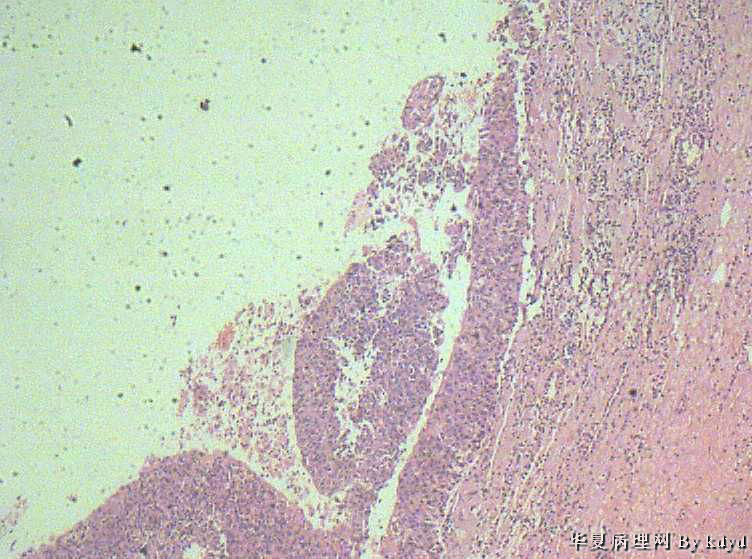

B3997左乳肿瘤--浸润性导管癌?

37岁,女。左侧乳腺肿块发现5个多月,伴隐痛。

手术见:肿块与周围组织分界不清,无明显包膜。

大体:不整形组织大小约3.5*35*2CM,未见明显包膜。质较软,切面浅黄色,一侧见一小囊腔直径约0.8CM囊壁较粗糙。

标签:乳腺浸润性导管癌 原位癌

浸润性乳腺导管癌?

囊壁内大量炎细胞浸润,囊壁被覆细胞有明显异型,可见核分裂,考虑癌,不知有无陷阱

考虑癌,但切片质量有点欠缺,发癌有点底气不足!

诊断乳腺浸润性导管癌确实有些担心,制片质量确实要提高,制作优良的切片,是正确诊断的前提。